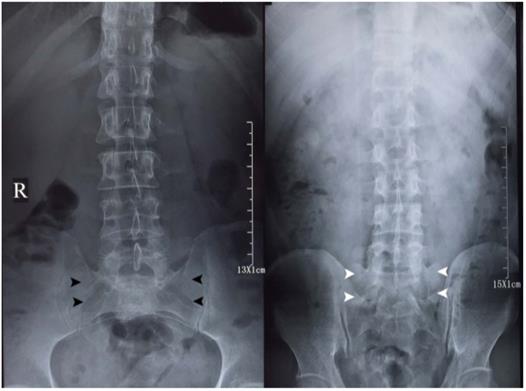

Importantly and surprisingly, the level of radiation exposure knowledge is relatively low for medical diagnostic imaging amongst both the medical professionals, patients and the general public, based on accumulating lines of evidence, i.e., multi-nations (US and Finland) cross-section surveys [6-8]. In clinical practice, low back pain is the most common disease second to influenza [9], both physicians and patients might concur on lumbar spine radiographs, without being aware of potential radiation exposure and the methodology for minimizing harmful effects, nor the red flag indicators [10]. Anterior-posterior (AP) projection plus lateral views (Figure 1, Figure 2) of the lumbar spine will lead to a radiation dosage of 3.7 mSv [11], over three-fold to the recommended safe criterion as 1 mSv for general population annually [1]. Therefore, there is an urgent need for medical professionals to propose the truth of radiation exposure and low radiation radiographic methodology, to benefit people globally.

Figure 1

Anterior-posterior (AP, left) and posterior-anterior (PA, right) projection lumbar spine radiographs of a member of the studying group (Dr. Chi-Jiao Ma). The imaging quality of both radiographs is relatively comparable for diagnostic purpose of lumbar spine morphology. AP projection lumbar spine radiograph is characterized by sacral holes (black arrowheads). The hallmark of PA projection lumbar spine radiograph is the visualization of sacrum (white arrowheads).